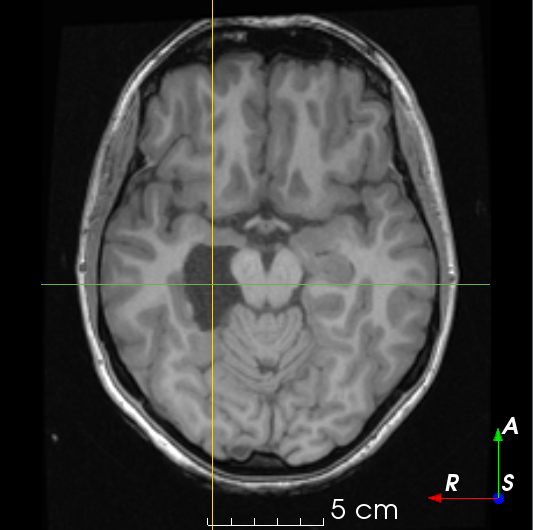

In the context of brain resection, the cavity fills with cerebrospinal fluid (CSF) after surgery [26]. This causes an inherent uncertainty in resection cavity delineation when adjacent to sulci, ventricles, arachnoid cysts or oedemas, as there is no intensity gradient separating the structures. Moreover, brain shift can occur during surgery, causing regions outside the cavity to fill with CSF.

If 𝑴Esubscript𝑴𝐸\bm{M}_{E} is used as the final mask, the resection might span both hemispheres or include non-realistic tissues such as bone or scalp (Fig. 1b). To eliminate this unrealistic scenario, a ‘resectable hemisphere mask’ is generated from the parcellation as 𝑴R(𝒑)=1subscript𝑴𝑅𝒑1\bm{M}_{R}(\bm{p})=1 if 𝑮(𝒑){𝑴BG,𝑴B,𝑴C,𝑴H^}𝑮𝒑subscript𝑴𝐵𝐺subscript𝑴𝐵subscript𝑴𝐶subscript𝑴^𝐻{\bm{G}(\bm{p})\neq\{\bm{M}_{BG},\bm{M}_{B},\bm{M}_{C},\bm{M}_{\hat{H}}\}} and 00 otherwise, where 𝑴BGsubscript𝑴𝐵𝐺\bm{M}_{BG}, 𝑴Bsubscript𝑴𝐵\bm{M}_{B}, 𝑴Csubscript𝑴𝐶\bm{M}_{C} and 𝑴H^subscript𝑴^𝐻\bm{M}_{\hat{H}} are the sets of labels in Z𝑍Z corresponding to the background, brainstem, cerebellum and contralateral hemisphere, respectively. 𝑴Rsubscript𝑴𝑅\bm{M}_{R} is smoothed using a series of binary morphological operations (Fig. 1c). The final resection label used for training is 𝒀R(𝒑)=𝑴E(𝒑)𝑴R(𝒑)subscript𝒀𝑅𝒑subscript𝑴𝐸𝒑subscript𝑴𝑅𝒑\bm{Y}_{R}(\bm{p})=\bm{M}_{E}(\bm{p})\bm{M}_{R}(\bm{p}) (Fig. 1d).

To generate a realistic CSF texture, we create a ventricle mask 𝑴V:Ω{0,1}:subscript𝑴𝑉Ω01{\bm{M}_{V}:\Omega\to\{0,1\}} from 𝑮𝑮\bm{G}, such that 𝑴V(𝒑)=1subscript𝑴𝑉𝒑1\bm{M}_{V}(\bm{p})=1 for all 𝒑𝒑\bm{p} within the ventricles and 𝑴V(𝒑)=0subscript𝑴𝑉𝒑0\bm{M}_{V}(\bm{p})=0 outside. Intensity values within ventricles are assumed to have a normal distribution [9] with a mean μCSFsubscript𝜇𝐶𝑆𝐹\mu_{CSF} and standard deviation σCSFsubscript𝜎𝐶𝑆𝐹\sigma_{CSF} calculated from voxel intensity values in 𝑰MRI(𝒑):𝒑Ω,𝑴V(𝒑)=1:subscript𝑰𝑀𝑅𝐼𝒑formulae-sequencefor-all𝒑Ωsubscript𝑴𝑉𝒑1\bm{I}_{MRI}(\bm{p}):\forall\bm{p}\in\Omega,\bm{M}_{V}(\bm{p})=1. A CSF-like image 𝑰CSF:Ω:subscript𝑰𝐶𝑆𝐹Ω{\bm{I}_{CSF}:\Omega\to\mathbb{R}} is then generated as 𝑰CSF(𝒑)𝒩(μCSF,σCSF),𝒑Ωformulae-sequencesimilar-tosubscript𝑰𝐶𝑆𝐹𝒑𝒩subscript𝜇𝐶𝑆𝐹subscript𝜎𝐶𝑆𝐹for-all𝒑Ω\bm{I}_{CSF}(\bm{p})\sim\mathcal{N}(\mu_{CSF},\sigma_{CSF}),\forall\bm{p}\in\Omega, and the resected image (Fig. 1e) is the convex combination: